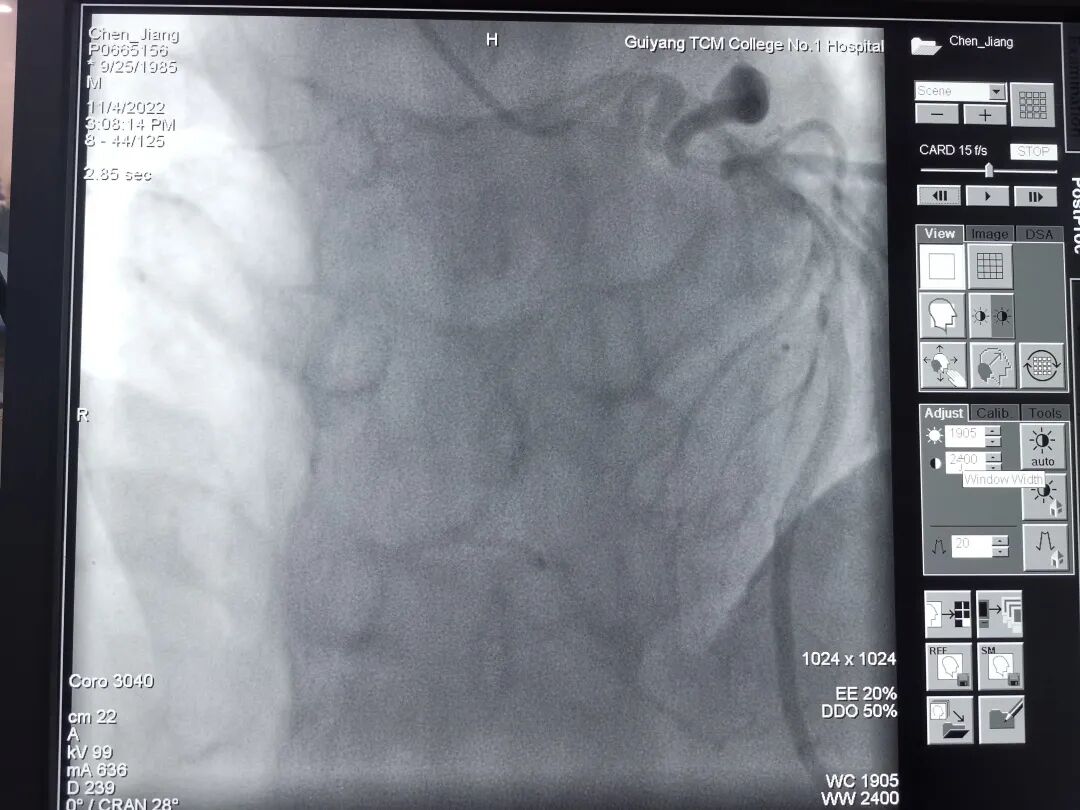

37岁的陈先生,因“胸闷、胸痛4月,加重10天”于11月1日收入我院心血管内科病区,从心电图及心脏彩超结果分析,患者具备冠脉造影的强适应征。郑涛副主任医师仔细查看病人,询问病史、症状,结合体征、检查结果,建议行冠脉造影术,并详细解释手术过程、风险,打消患者顾虑。2022年11月04日行冠脉造影术:术中穿刺右侧桡动脉后造影导管顺利进入左冠脉,造影示左冠状动脉先天性冠状动脉瘘,并可见左冠向右冠远端的逆向血流,而因患者主动脉弓异常扭曲,常规造影导管及专用右冠造影导管反复尝试多次均无法找到右冠脉开口,考虑患者的右冠状动脉开口变异,遂使用猪尾巴导管链接高压注射器造影后隐约显示右冠开口位置,因造影耗时近2小时,为保证患者安全,暂时先下台,准备再次择期手术。

猪尾巴导管高压注射器造影隐约显示右冠开口位置